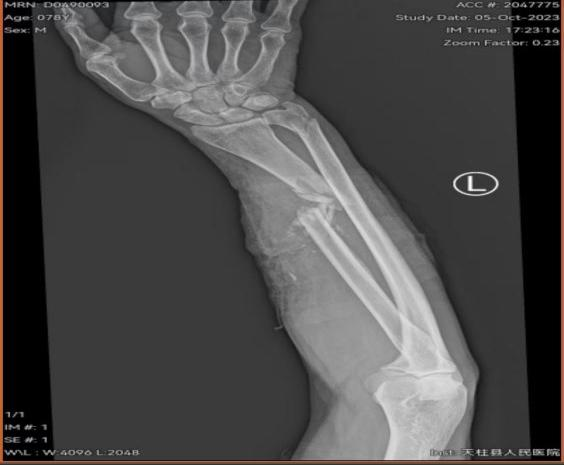

患者金某某,男,78岁,因在家使用电锯锯柴时不慎被电锯锯伤左前臂,血流不止、疼痛难忍,当时患者家属考虑手术难度大希望转诊上级医院治疗但又考虑到转时间过长风险因素高,在左右为难之际,患者一家属联系到天柱县中医院骨科学科带头人、主任医师张平院长,张平院长知悉情况后,征得患者及家属同意,通过急诊120转诊到天柱县中医院并开通绿色通道办理入住到天柱县中医院骨伤科。

在张平院长的带领下,天柱县中医院骨伤科及手术室麻醉科团队建立绿色急诊快速通道经过三个多小时的手术,患者手术满意顺利安返病房。术后患者及家属非常感激,直言天柱县中医院医师敢于担当、技术过硬、为民解忧,在家门口就能解决高难度手术。术后骨伤科医护团队继续为该患者进行专业的专科治疗护理。目前患者已经顺利康复出院了。